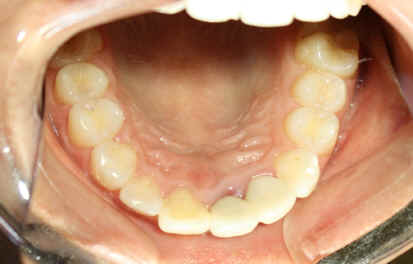

Comprehensive Treatment

23 year-old female, "I want braces"

Dental history: #9 fracture at age of 8; #9,10 crowns (joined) 2 years ago; #9 has chronic apical infection, #19 extracted due to caries at age of 15

#18 mesiolingual tilt, #19 traditional implant and extract #17; once #19 implant is osteointegrated, it is to be used as an anchorage to upright #18, elastics between #15 buccal hook and 18 lingual button to correct linguoversion of #18

#14 supraeruption, mini-implants, orthodontic intrusion

Start tradtional orthodontic treatment